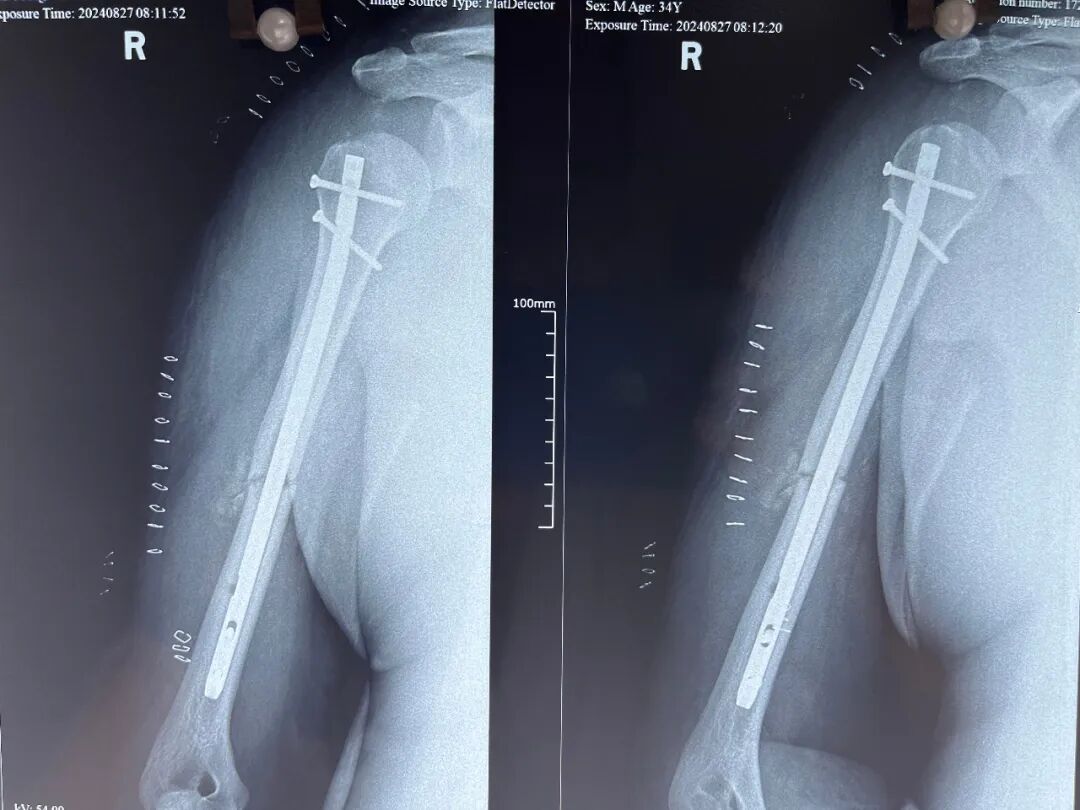

经过深入研讨和严谨分析,最终确定了完善的手术和麻醉方案。随后,在全麻状态下,成功为王先生实施了右侧肱骨干骨折髓内钉固定术。手术与麻醉过程进展十分顺利。术后,王先生安全度过了呼吸暂停危险期。

△ 右侧肱骨干骨折髓内钉固定术术后

从术前的细致检查与精心筹备,到手术中的专业操作与高度专注,再至术后的贴心护理与耐心康复指导,每一个环节都饱含着医护人员的心血与付出。他们不仅时刻关注患者的骨折康复情况,还对呼吸暂停综合症可能带来的风险保持高度警觉,全力确保患者能够安全、顺利地恢复健康。